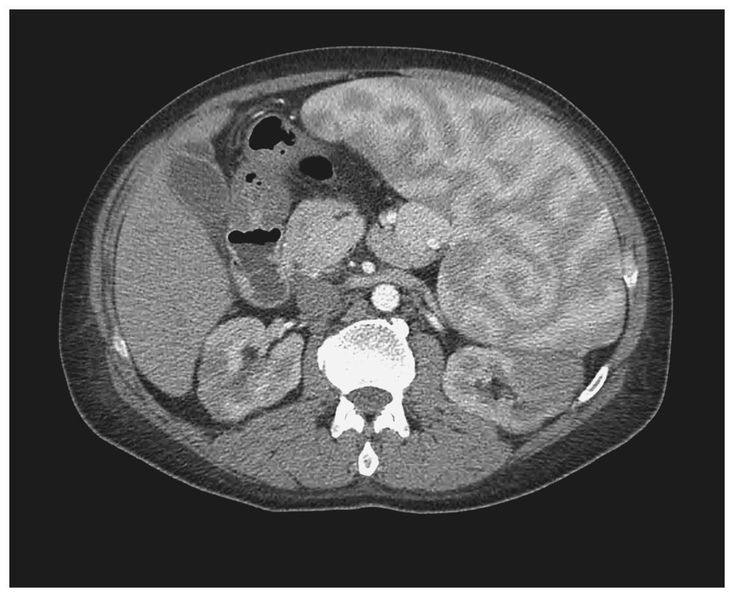

A 50-year-old man with a history of warm-antibody autoimmune hemolytic anemia and splenomegaly presented with fatigue of 2 weeks' duration and the recent onset of jaundice. Physical examination revealed scleral icterus, conjunctival pallor, and splenomegaly. Laboratory tests revealed a hemoglobin level of 4.8 g per deciliter, a hematocrit of 14.3%, a white-cell count of 3200 per cubic millimeter, and a platelet count of 42,000 per cubic millimeter. Treatment with prednisone and intravenous immune globulin was initiated, and the patient underwent transfusion with multiple units of packed red cells during his hospital stay. Computed tomography of the abdomen with the use of nonionic contrast material revealed an enlarged spleen (25.4 cm craniocaudally, 18.1 cm anteroposteriorly, and 22.5 cm transversely) with a heterogeneous pattern. This pattern was seen during the initial 60 seconds after the injection of contrast material. It has previously been described as a series of alternating bands of high and low attenuation due to variability in blood flow between the red and white pulp of the spleen. The prominence of the heterogeneous pattern in this spleen is due to splenomegaly. The patient subsequently underwent splenectomy; a small monoclonal B-cell population was identified by means of flow cytometry. The patient's leukopenia and thrombocytopenia resolved (white-cell count, 10,500 per cubic millimeter; platelet count, 178,000 per cubic millimeter), and the hemoglobin level stabilized at more than 10.0 g per deciliter.